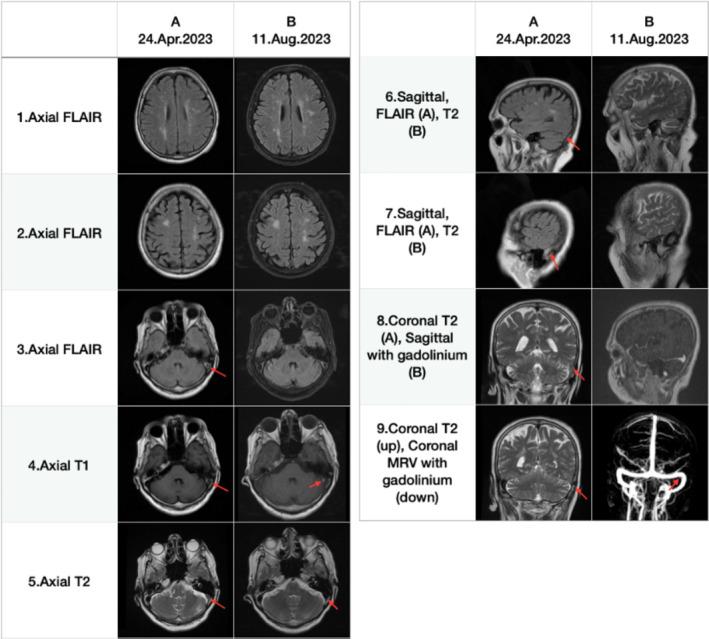

Cerebrovascular thrombosis is among the most critical medical conditions, making early diagnosis and management crucial. Although some symptoms of cerebrovascular thrombosis are typical and lead to early diagnosis, they can sometimes present with rare and unusual symptoms, complicating the diagnostic process. Given the morbidity and mortality associated with these events, it is important to be aware of unexpected symptoms to diagnose and manage these patients more accurately and rapidly. We report a 74-year-old female initially misdiagnosed with Alzheimer's because of cognitive decline and disorganized speech. Her symptoms did not improve with Alzheimer's treatment. She was reevaluated by a neurologist, and her cognitive test results were impaired. Her brain MRI revealed a previously undetected left transverse sinus cerebral venous thrombosis with subcortical white matter lesions. The patient was managed acutely with subcutaneous enoxaparin and transitioned to oral rivaroxaban, resulting in significant improvement. This case report aimed to draw attention to the pitfalls of diagnosing dementia-like syndromes in the elderly, advocating for a systematic approach to differential diagnosis. It emphasizes that a collaborative effort between psychiatrists, neurologists, radiologists, and other healthcare members is essential for accurate diagnosis and timely intervention, which can significantly alter the management and outcome for the patient.

脑血管血栓形成是最危急的病症之一,早期诊断和治疗至关重要。虽然脑血管血栓形成的一些症状较为典型,可实现早期诊断,但有时也会出现罕见和不寻常的症状,使诊断过程变得复杂。鉴于这些病症的发病率和死亡率,了解意外症状对于更准确、快速地诊断和治疗这些患者非常重要。我们报告了一名74岁女性,最初因认知能力下降和言语紊乱被误诊为阿尔茨海默病。接受阿尔茨海默病治疗后,她的症状并未改善。一名神经科医生对她进行了重新评估,其认知测试结果显示受损。她的脑部磁共振成像(MRI)显示左侧横窦脑静脉血栓形成,伴有皮质下白质病变,此前未被发现。该患者接受了皮下注射依诺肝素的急性治疗,并过渡到口服利伐沙班,病情显著改善。本病例报告旨在提醒人们注意老年痴呆样综合征诊断中的陷阱,提倡采用系统的鉴别诊断方法。它强调精神科医生、神经科医生、放射科医生和其他医护人员之间的协作对于准确诊断和及时干预至关重要,这可以显著改变患者的治疗和预后。